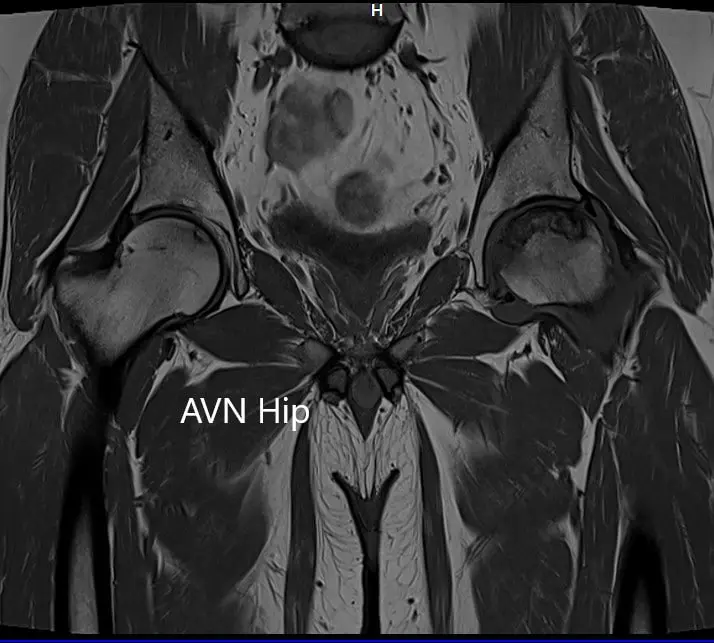

Imaging studies obtained in the form of an X-Ray suggested sclerosis of the left head of the femur. There were marked acetabulum changes. An MRI was further obtained suggesting avascular necrosis of the superior lateral head of the femur with changes in the acetabulum. There was marked hypointense areas on both T1WI and T2WIs.

T1WI coronal section of MRI showing AVN hip

T1WI coronal section of MRI showing AVN hip.